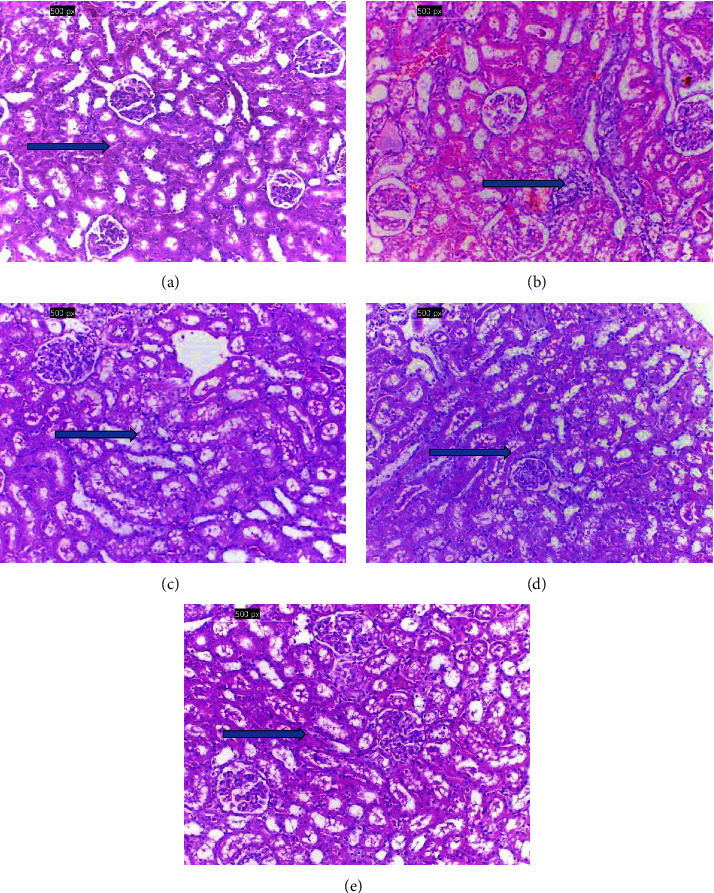

The purpose of this study was to test the protective effect of Withania somnifera (WS) against the harmful effects of mercuric chloride (HgCl2)-induced kidney failure at the histological, biochemical, and immune levels in Wistar rats. The study assessed the biochemical and immunological changes in five groups (n = 6): Group 1 (G1) was the negative control, and the other rats received a single subcutaneous dose of HgCl2 (2.5 mg/kg in 0.5 mL of 0.9% saline solution) and randomly divided into 4 groups. Group 2 (G2) was the positive control and left without treatment. Groups 3, 4, and 5 (G3, G4, and G5) were treated with different doses of WS root powder for 30 days. The HgCl2-positive group showed significant signs of renal toxicity as reflected by increased levels of kidney function parameters (blood urea nitrogen, urea, and creatinine), inflammatory biomarkers, immunological indices (SDF-1, IL-6, NGAL, and KIM-1), and oxidative stress (SOD, TAC, CAT, GSH, and MDA). The positive group rats also showed drastic pathological changes in renal tissues. Different doses of WS treatment significantly reduced the levels of all biochemical markers and decreased pathological damage to the kidney tissues. The antioxidant, phenolic, and flavonoid constituents of WS root powder helped protect rats' kidneys against HgCl2-induced kidney toxicity in male rats.